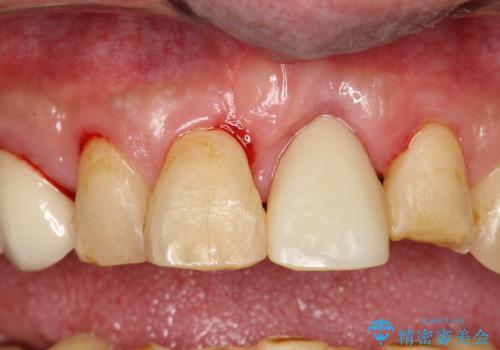

左上1が水平的に割れている状態で、歯冠を取り除くと神経が露出しており、唇側はかなり歯肉縁下で破折しており、そのままではかぶせものを入れるのは難しい状態でした。

根管治療をした上で歯を引っ張りだして(エクストリュージョン)、その後、骨外科にて歯周組織を整えた上で、かぶせものを入れていく治療計画をたてました。